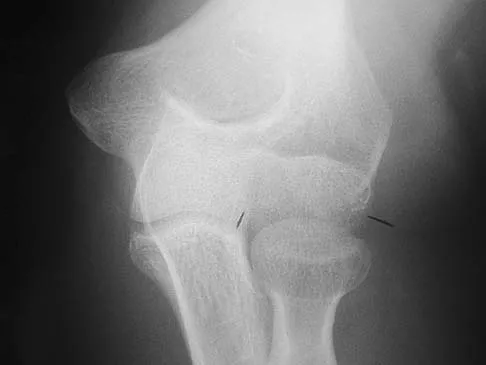

Question 12

Figure 12 shows a lateral radiograph of the elbow. What is the most likely diagnosis?

Explanation